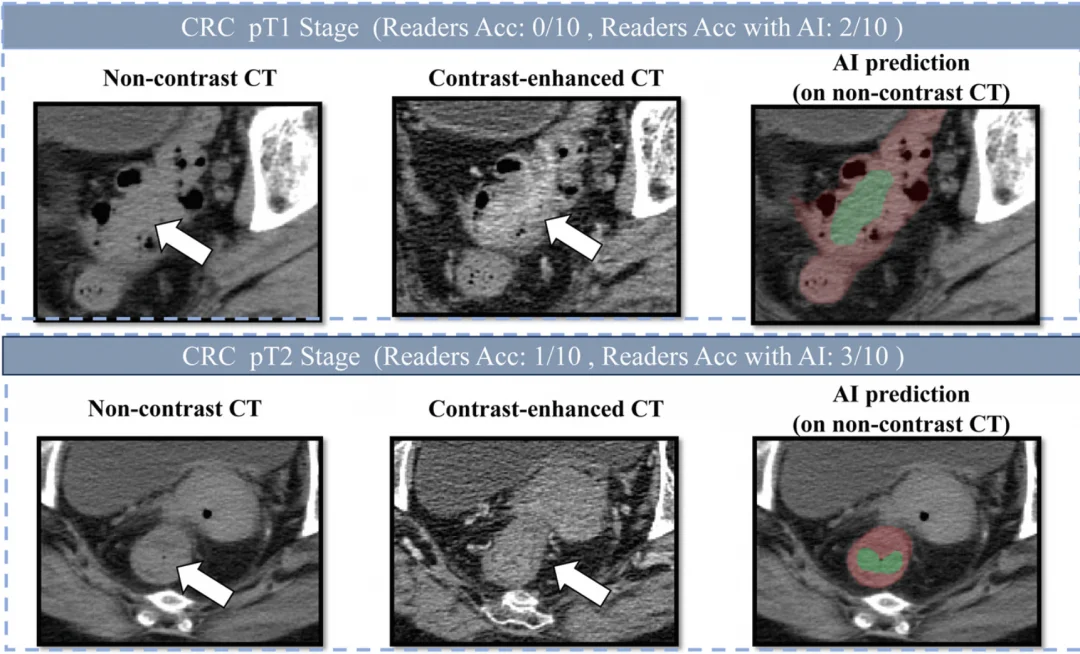

所以当研究团队邀请10位医生参与人机对照实验时,医生们甚至都有点茫然——这超出了他们的临床经验。

延续前面两个癌种的技术积累,DAMO COCA模型采用了"先定位、后诊断"的两阶段深度学习架构:第一步精确分割出形态复杂的肠道器官——这一步对AI本身就是挑战;第二步对可疑区域逐一精细判断。为了提升对早期小肿瘤的识别能力,团队还针对小于3厘米的病灶做了重点训练。

训练数据的构建更是一场硬仗。医生没法直接在平扫CT上标注肠癌——因为人眼看不清。团队的办法是:先请医生在增强CT(注射造影剂后对比度更高的影像)上精确勾画肿瘤位置,再通过图像配准技术"投射"到平扫CT上。